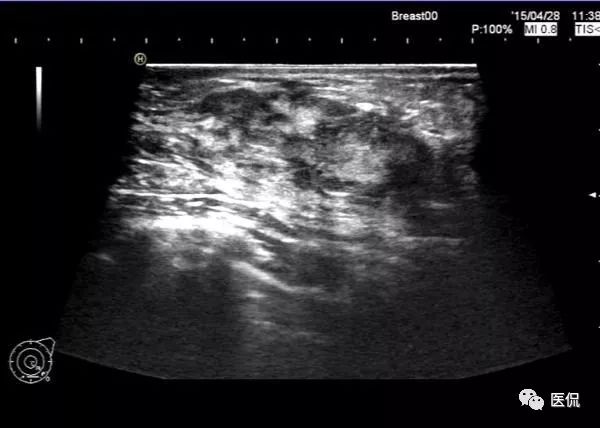

超声超声检查设备为HITACHI Avius彩色多普勒超声诊断仪,频率3-13MHz,患者取仰卧位,暴露双侧乳腺及腋窝,对每侧乳腺采取扇形扫描,充分检查每一区域。

本病例特点为年轻女性,以发现左乳肿块1+月就诊,病程较短,有先天性乳头内陷。X钼靶显示左乳外下象限腺体结构紊乱,密度增高,边缘模糊,无钙化,腋窝无增大淋巴结。超声显示病灶范围较为广泛,为混杂低回声区,边缘不清。MRI显示病灶呈片状稍长T2信号,边缘不清,DWI(b=600)为稍高信号,增强后明显不均质强化,时间-信号曲线为平台型。上述影像表现均提示病变范围广泛,边界模糊不清,无肿块显示,结合患者先天性左乳头凹陷,有乳腺炎发病基础,因此在诊断上首先需要考虑浆细胞性乳腺炎的可能性。

乳腺X线摄影是基本检查方法,主要表现为患侧乳腺的大片密度增高,边缘不清,有时可在病灶区域内看到迂曲透亮的扩张导管影。超声可清晰显示扩张的导管,浆细胞性乳腺炎一般分为三型:(1)包块型,肿块多位于乳晕附近,边界不清,形态不规则,与乳腺癌不易鉴别;(2)单纯导管扩张型:乳腺腺体内见多发扩张导管,内透声差;(3)脓肿形成型:范围较广泛,边界模糊,脓肿形成后深压探头可显示脓液流动,光点漂浮。MRI检查具有较好的组织分辨率及空间分辨率,能从多个角度显示病灶的信号、形态特点,T1WI呈等低信号,压脂T2WI呈高信号,动态增强呈不均匀明显强化,脓肿形成后脓肿壁环形强化,DWI脓腔呈明显高信号,时间-信号强度曲线多为I型或II型。对与乳腺癌鉴别具有较大意义。